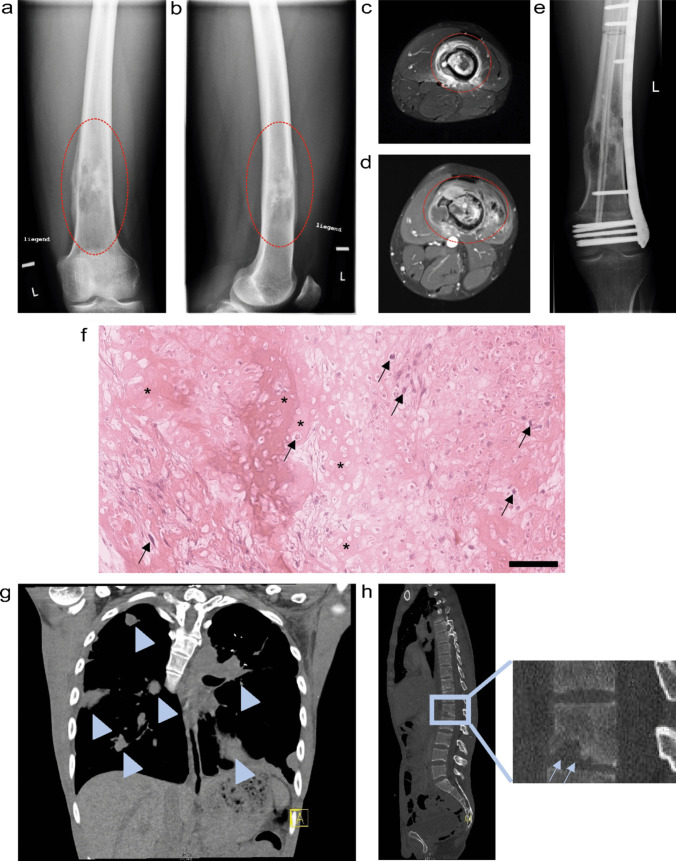

骨肉瘤是最常见的恶性骨肿瘤,主要影响儿童和年轻人。对于这些年轻患者来说,骨肉瘤目前的治疗方案给日常生活带来了很大的限制,而且发病率高、存活率低。尽管研究工作一直在进行,但在过去 40 年中,首次确诊且无转移的患者的 5 年生存率一直没有变化。目前,对新型疗法的需求仍未得到满足,尤其是对有效的二线疗法的需求。因此,迫切需要先进的临床前模型和药物测试平台,以考虑复杂的疾病特征、肿瘤的高度异质性以及与骨微环境的相互作用。在本综述中,我们将全面概述骨肉瘤的最新组织工程和患者特异性模型。这些用于晚期治疗试验的先进平台旨在通过以更准确、更复杂的方式模拟患者的疾病状态,改善未来患者的治疗效果,从而提高临床前研究的质量。

Osteosarcoma is the most common malignant bone tumor, primarily affecting children and young adults. For these young patients, the current treatment options for osteosarcoma impose considerable constraints on daily life with significant morbidity and a low survival rate. Despite ongoing research efforts, the 5-year survival rate of first-diagnosed patients without metastases has not changed in the past four decades. The demand for novel treatments is currently still unmet, in particular for effective second-line therapy. Therefore, there is an urgent need for advanced preclinical models and drug-testing platforms that take into account the complex disease characteristics, the high heterogeneity of the tumour and the interactions with the bone microenvironment. In this review, we provide a comprehensive overview about state-of-the-art tissue-engineered and patient-specific models for osteosarcoma. These sophisticated platforms for advanced therapy trials aim to improve treatment outcomes for future patients by modelling the patient's disease state in a more accurate and complex way, thus improving the quality of preclinical research studies.